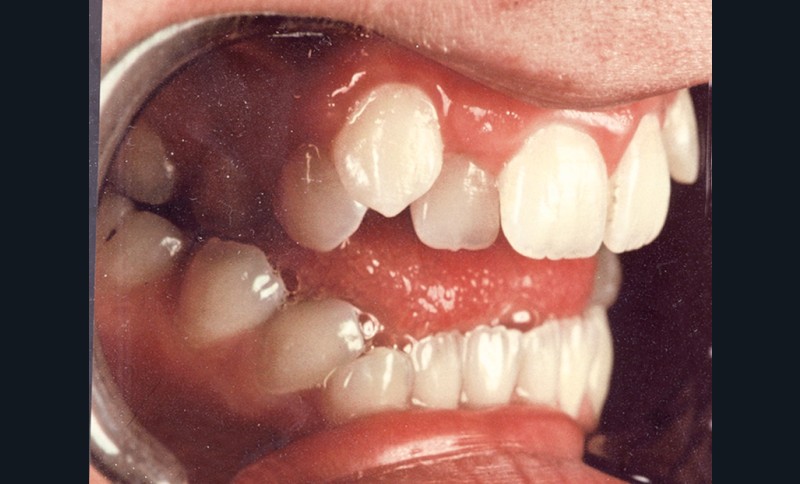

Au niveau squelettique, elle présente une classe I associée à une endognathie maxillaire et une hyperdivergence mandibulaire majeure liée à un excès de croissance alvéolaire verticale postérieure maxillaire et une inclinaison mandibulaire très marquée (fig. 1 et 3).

Sur le plan occlusal et dentaire, on observe une classe I molaire, une occlusion transversale en bout à bout à droite et inversée à gauche et une béance antérieure sévère s’étendant jusqu’aux molaires. Un encombrement est présent aux deux arcades avec des dystopies canines importantes (fig. 2).